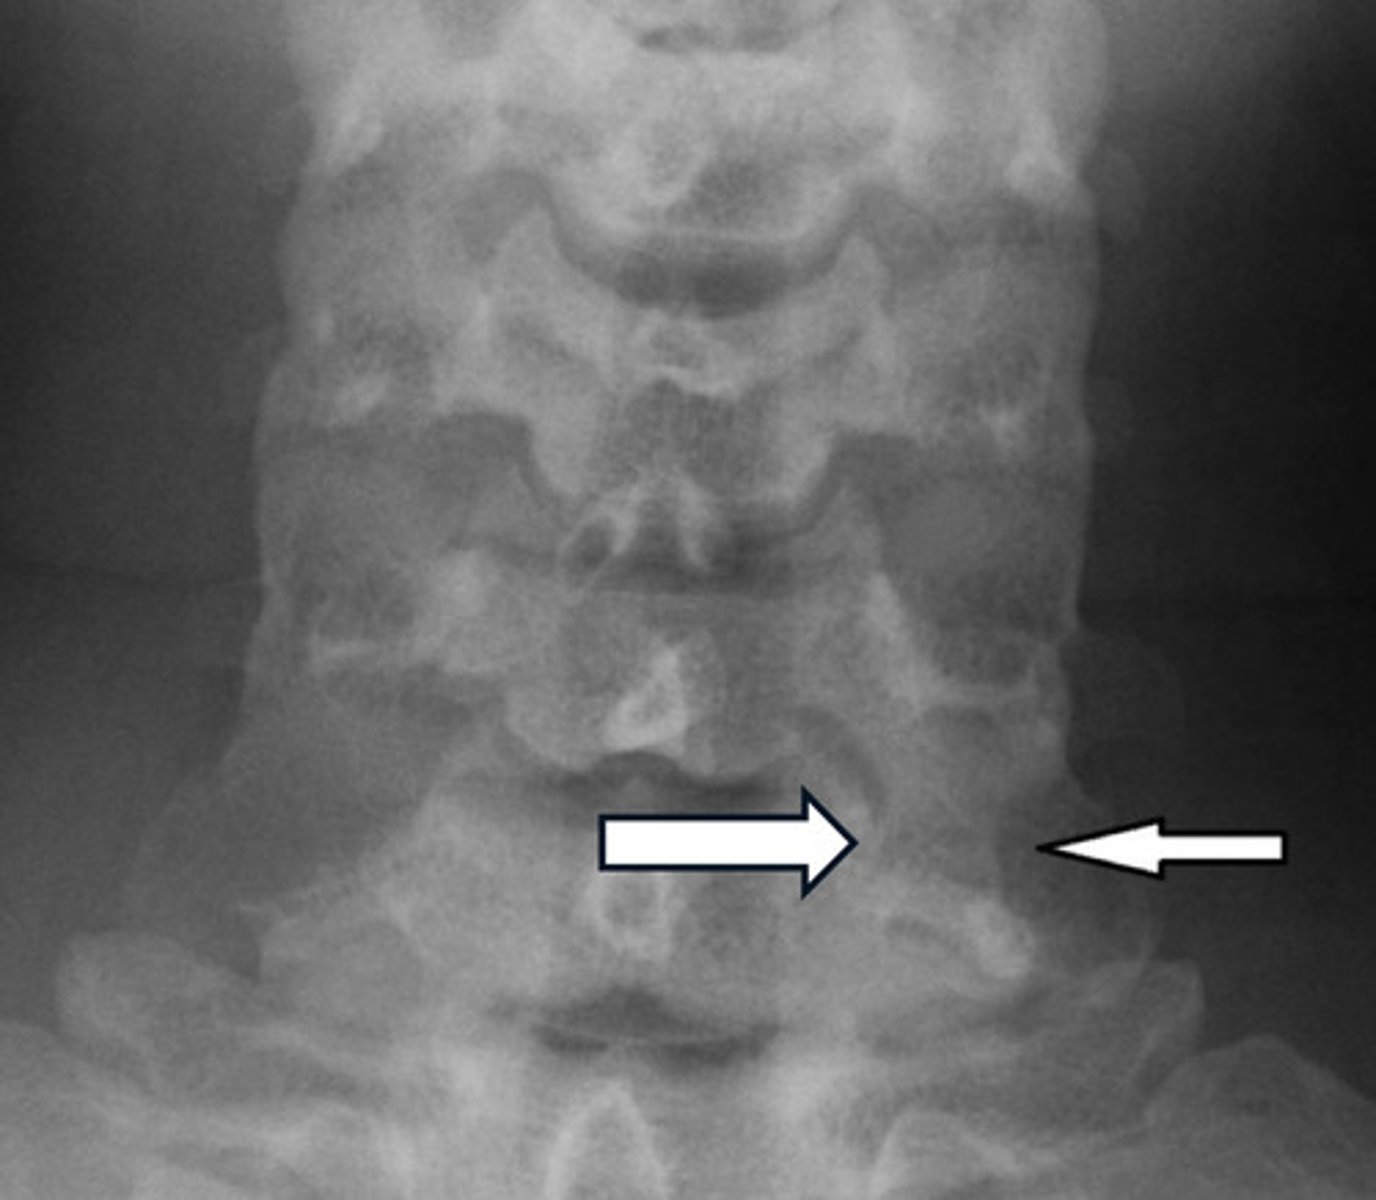

Sacralization vs Lumbarization

Sacralization = L5 doesn't fully segment from the sacrum (looks S1-like)

Lumbarization = S1 does not fully segment from L5 (looks L6-like)

COMPLETE lumbarization vs sacralization

Complete lumbarization = 6 lumbar segments (S1 separated from sacrum)

Complete sacralization = only 4 lumbars (L5 fused with sacrum)

Image example of sacralization of L5